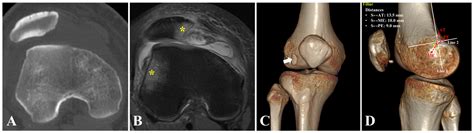

• Imaging Studies: X-rays, MRI, and CT scans can provide detailed images of the knee joint, helping to identify any structural abnormalities, fractures, or soft tissue injuries. MRI is particularly useful for visualizing the MPFL and other ligaments.

• medial patellofemoral ligament mri